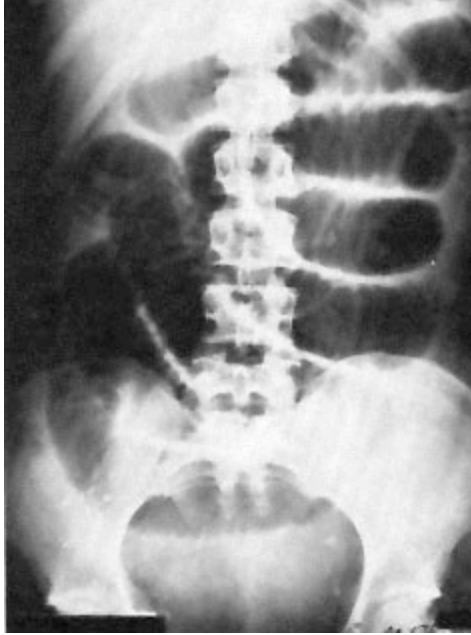

A 42-year-old woman comes to the physician because of nausea and vomiting and abdominal cramping and swelling over the past 12 hours. She takes an oral contraceptive. She underwent an appendectomy 5 years ago. Abdominal examination shows distention and moderate tenderness without guarding. An x-ray of the abdomen is shown. Which of the following is the most likely diagnosis?